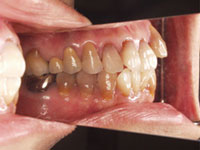

1. 根っこの治療を行う

2. 歯の表面を少し削りジルコニアクラウンの被せ物をする

完成後の写真.

歯の形、色、位置、見え方、笑った時、会話をするときに美しく見える口元を改善する治療方です。歯冠長を延長してセラミックス等の被せ物を入れることで歯の位置や見た目を改善します。